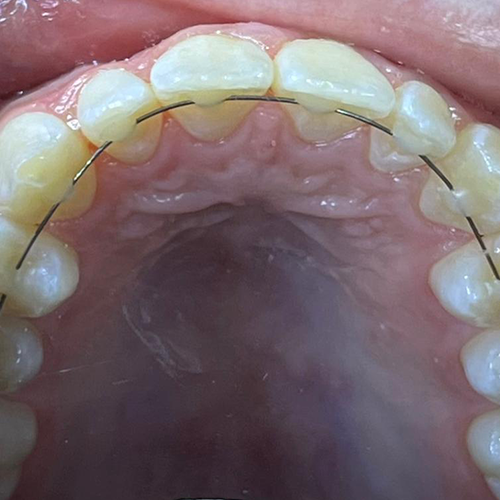

Comprueba en la práctica cómo el conocimiento se transforma en resultados reales a través de los casos de nuestros alumnos.

SALA DE PROCEDIMIENTOS

Siga clases prácticas y la evolución de casos clínicos reales directamente desde la clínica del Dr. Ary Nunes.